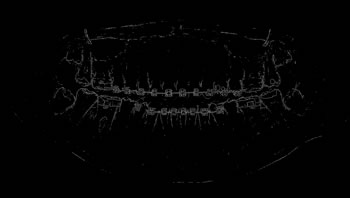

Refer to caption

Determining ROI

For each image, after the annotation of the teeth, the buccal region was also annotated, covering the whole region delineated by the contour of the jaws. This process was carried out in view of preserving the area containing all the teeth (objects of interest). Finally, the region of interest (ROI) was determined by multiplying the values of the pixel array elements, representing the original panoramic X-ray image, by its corresponding binary matrix, resulting from the process of oral annotation. Figure 5 illustrates the whole process to determine the ROI of the images.